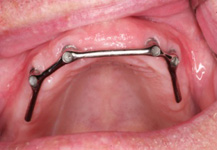

Bezzubá čelist je hlavní indikací pro ošetření pomocí implantátů. Zejména celkové zubní náhrady v dolní čelisti mají velice nízkou stabilitu a držení díky velkému úbytku kosti.

S pomocí zubních implantátů můžeme díky různým kotevním systémům (třmeny, kulové hlavy, Locatory) zajistit stabilitu a držení protézy nebo při použití většího počtu implantátů zhotovit pevné náhrady – můstky nalepené nebo našroubované na pevno na implantáty.

S těmito typy náhrad můžeme dosáhnout perfektní funkci, výbornou estetiku, fonetiku a současně zajistit u pacienta možnost dobré hygienickou péče a čištění, která je pro životnost implantátů velice důležitá.